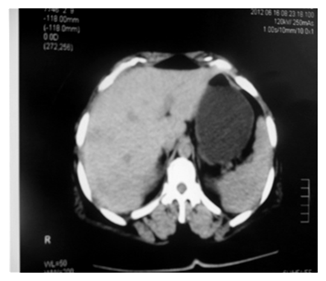

Abdominal

ct scan before (figure 2), and with

opacification confirmed this cholecystitis with a heterogeneous liver with

multiple rounded hypodense microlesions, slightly enhanced after injection of

contrast product (figure 3 images a and

Figure 2. Abdominal scan in sagittal section without injection of the product showing hypodense formations

Figure 3. Abdominal scan after injection of contrast product in axial section showing contrast enhancement of liver nodules.